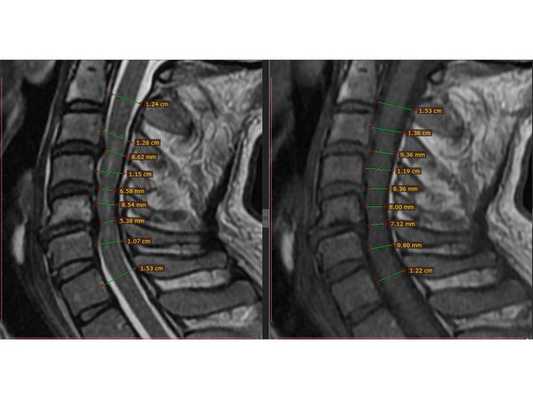

КТ пояснично-крестцового отдела позвоночника показала состояние после перенесённого спондилодисцита L2-L3 (воспалительного заболевания инфекционного характера) с разрушением тела L3 позвонка и кифотической деформацией (искривлением позвоночника) на данном уровне.

Состояние после перенесённого спондилодисцита L2, L3 позвонков с формированием абсолютного стеноза (критического сужения просвета в позвоночном столбе) на уровне L2-L3 и развитием нижнего парапареза

После операции в неврологическом статусе наблюдается положительная динамика: умеренный парапарез в нижних конечностях почти полностью регрессировал, жалобы на "онемения в ногах" также исчезли. На контрольной КТ видно состояние после успешной декомпрессии на уровне L2-L3 и установки транспедикулярной фиксирующей системы на уровне L1-L4.

Учитывая анамнез и результаты КТ пояснично-крестцового отдела позвоночника, можно предположить, что во время стационарного лечения у пациентки на уровне L2-L3 позвонков развился спондилодисцит. Характерным признаком этого заболевания в острой фазе является уменьшение рентгеновской плотности тел позвонков. Но во время проведения компьютерной томографии плотность тел L2 и L3 позвонков была высокой, что свидетельствовало о завершении воспалительного процесса и склерозировании тел позвонков. Вероятнее всего, антибактериальное лечение погасило воспаление не только в брюшной полости и почках, но и в позвоночнике. Однако после выписки из больницы, при переходе из лежачего положения в вертикальное, у пациентки стала увеличиваться кифотическая деформация. Патология привела к образованию стеноза позвоночного канала на уровне L2-L3, что и спровоцировало возникновение нижнего парапареза. С помощью транспедикулярной фиксации L1-L4 и декомпрессии на уровне L2 удалось устранить неврологические симптомы и стабилизировать позвоночный сегмент, то есть "экстренная" помощь была оказана успешно.